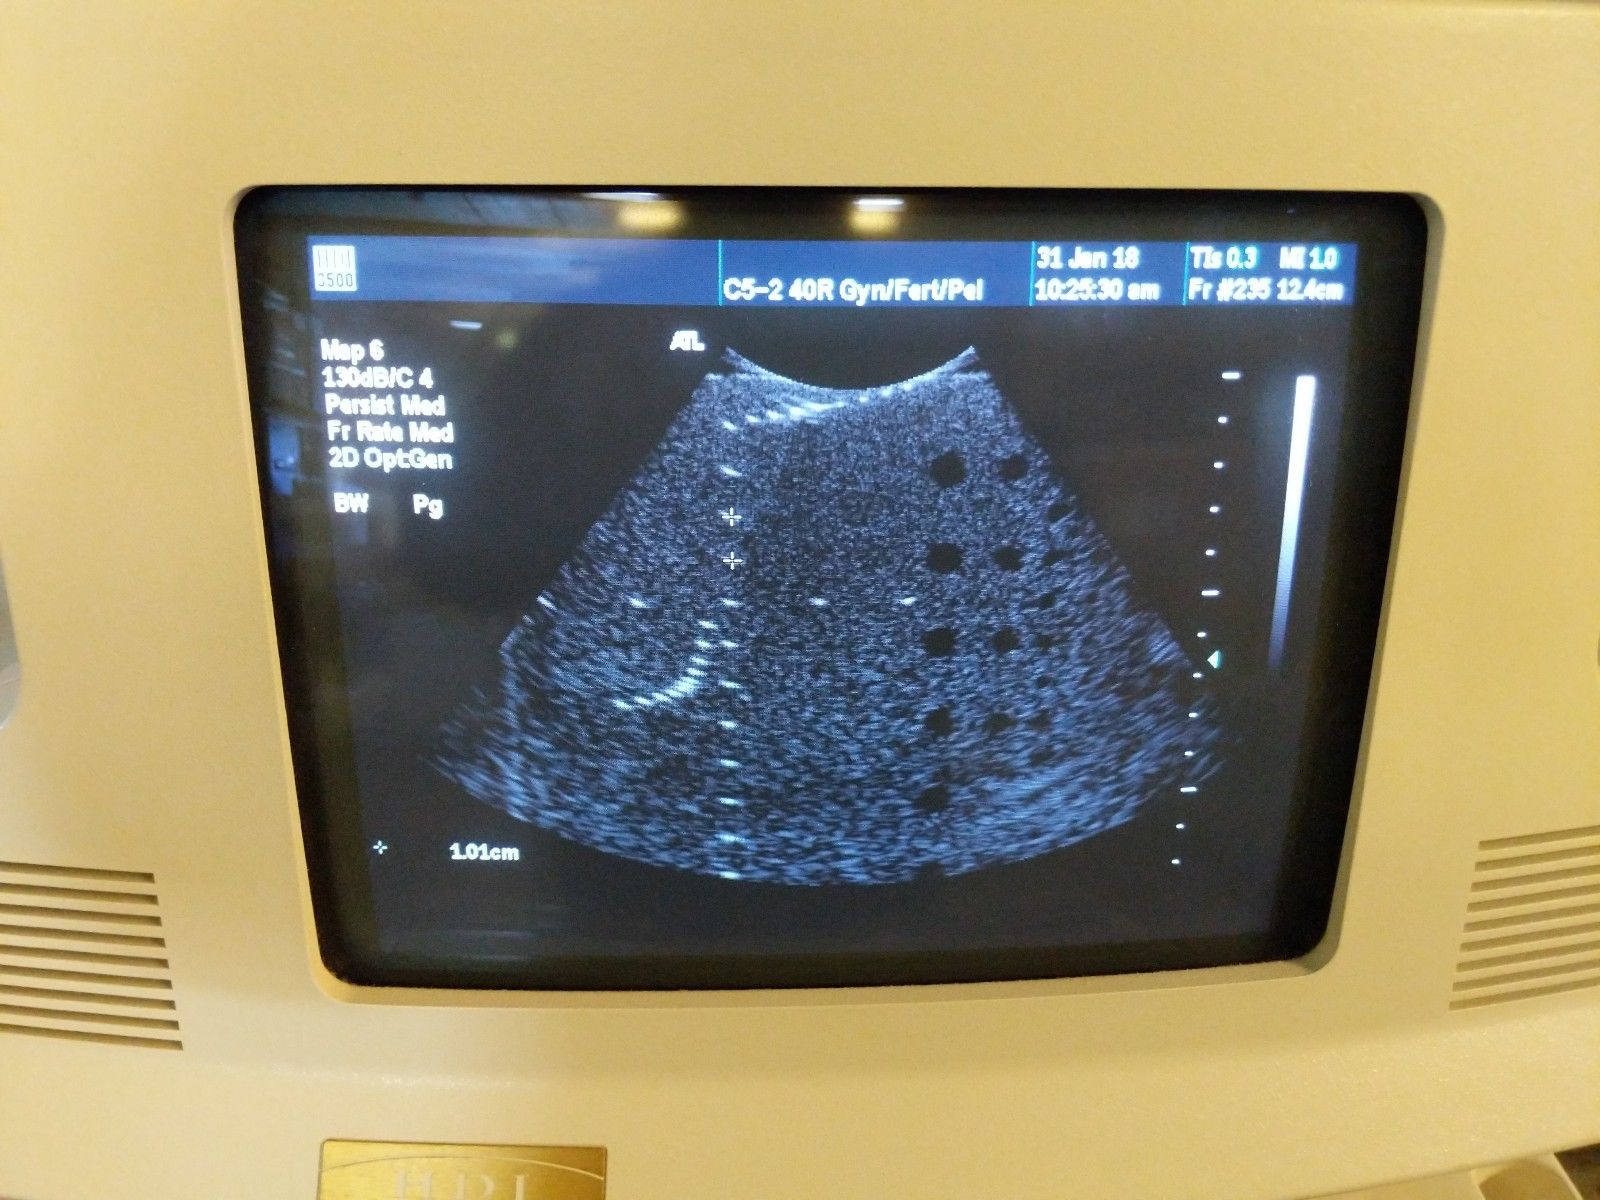

ATL HDI 3500 w/ 2 Probes

Condition:Used : An item that has been used previously. The item may have some signs of cosmetic wear, but is fully operational and functions as intended. This item may be a floor model or store return that has been used. See the sellerâs listing for full details and description of any imperfections. See all condition definitions- opens in a new window or tab

Seller Notes:âSystems have been powered on and tested. Additional tests may be performed. All systems will leave in described condition with no warranties expressed or implied.â

Brand: ATL

Model: HDI 3500